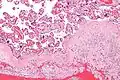

Micrograph of a chronic deciduitis, showing the characteristic plasma cells. H&E stain.

Chronic deciduitis is a type of long-lasting inflammation that arises in pregnancy and affects the endometrial stromal tissue (decidua).

It is associated with preterm labour.[1] The diagnosis rests primarily on the presence of plasma cells.[2]